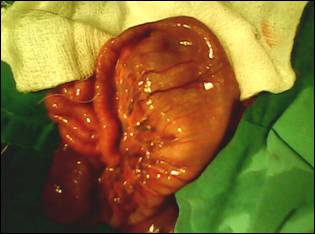

IMG0176A.jpg

Figure 2: Type-I jejunal atresia in the same patient.